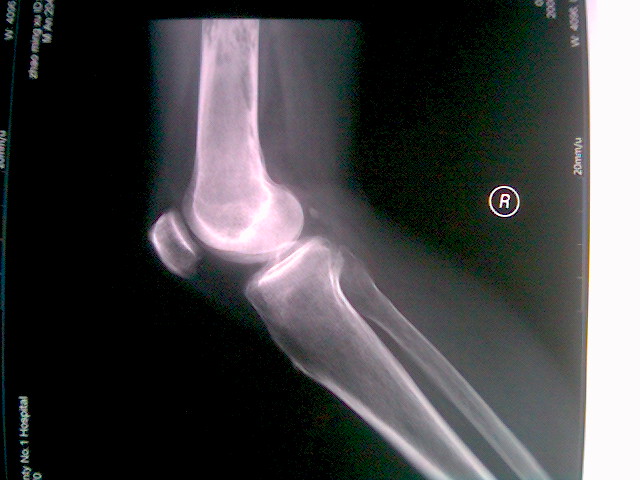

翻翻手机发现2年前在医院实习时,无意中拍下的片子`男大约60~65y把`以右膝关节痛为主诉来诊`带我的老师要求他住院`患者决绝了`后来老师说你不能下地走路了`在走就病理性骨折了`正好一周后的一天这个患者以`右股骨干骨折来诊`应了老师的话,因此,我对这个老师一直敬佩不已

右侧股骨中下段见多个大小不等的虫蚀样破坏区,病灶边缘较锐利,骨皮质完整,骨外形轮廓无改变,无骨膜反应,软组织无肿胀,脂肪层清晰。由于无病史提供,只能根据年龄及本片考虑第1骨囊肿,第2骨包囊虫病。

右股骨下段仅摄及股骨骨破坏区下部一小部分:股骨下段见片状、虫蚀状骨破坏,有骨膜反应,软组织肿胀不明显,应考虑:1、股骨下段骨髓瘤 2。股骨下段骨肉瘤

股骨干病变部位没有包括,老年男性,恶性病变,mm或转移

股骨中下交界段可见虫蚀样骨质破坏,考虑骨转移瘤可能性大。

考虑右股骨下段恶性肿瘤(转移瘤或骨髓瘤)。